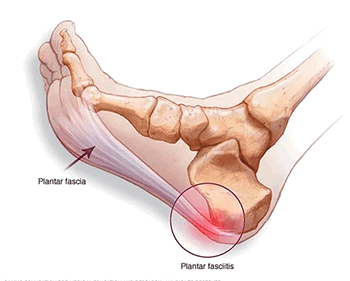

Резкая боль в области пятки - достаточно распространенное явление, ограничивающее двигательную активность, и вызывающее существенный дискомфорт. Очень часто причина болевого синдрома заключается в развитии подошвенного фасциита - заболевания, провоцирующего образование костного нароста. Чтобы избежать этой проблемы, важно своевременно обратиться к врачу и пройти диагностическое обследование.

Подошвенный фасциит - воспаление подошвенной фасции, выполняющей функции соединительной ткани для поддержания свода стопы. Патология носит небактериальный характер и возникает в результате частой чрезмерной нагрузки на фасцию. Болевой синдром локализируется в пятке и нижней части стопы, усиливаясь при первых шагах после продолжительного отдыха. В большинстве случаев подошвенный фасциит образуется на задней или нижней поверхности пяточной кости, что делает его схожим со шпорой. Наиболее часто это заболевание встречается у людей в возрасте от 40 лет, причем женщины предрасположены к нему больше, чем мужчины.